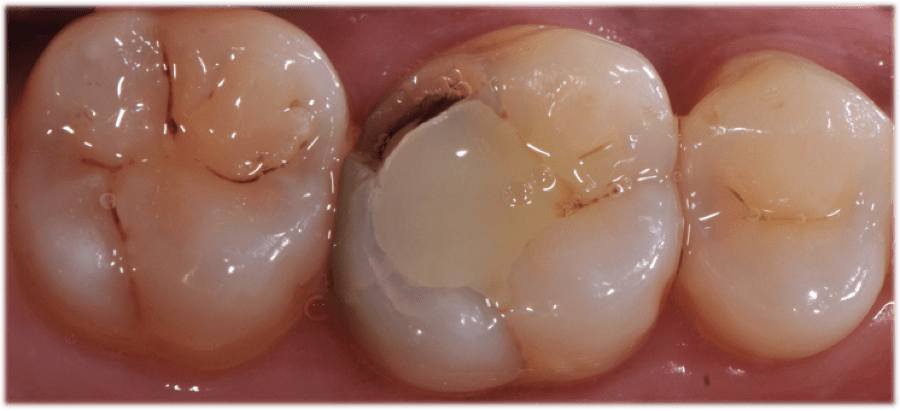

Taking a systematic approach to bur selection will streamline the chairside experience for the practitioner and the patient. In this case, I am prepping tooth No. 3 for a partial coverage restoration. It is a large filling with decay underneath. Whether it is partial (Figure 1) or full (Figure 2) coverage, preparation design should begin with the removal of the existing filling and any decay (Figure 3). This step is usually accomplished with the use of a Solo diamond double inverted cone. Once this step is complete, the clinician should either break contact with a flame or begin occlusal reduction with the football diamond. The preparation may require a build-up material to idealize the shape after the general form has been completed.

The preparation margins are then finished per the dental designer’s preference, which involves using burs and diamonds. The primary goal in bur selection is to choose a dependable, well-made, sterile, and predictable bur that will accomplish the best preparation. I prefer to use a shoulder preparation with a flat end taper, such as the Solo course grit 837012C or 837016C. The 12C and 16C signifies the diameter of the bur and is a useful tool in determining the amount of tooth reduction made on the axial walls. However, different clinical situations may require different burs, so dental designers should not limit themselves to one particular model or line.

It should be noted that Premier’s KR Modified Shoulder prep burs allow for a 90° margin with a rounded internal angle. This combination of burs allows me to prepare crowns, inlays, or onlays, and serves as my first choice for a restorative bur block. After tooth preparation is complete, the dentist must address whether retraction is needed. Clinicians can either place a retraction cord or use a paste retraction system like Traxodent® Hemodent™. Typically, I use both retraction cord and Traxodent, which better isolates the preparation for scanning and designing a CAD/CAM milled restoration. It also isolates the tooth for same day seating of the restoration, keeps the area clean before the procedure, and assists in a fast, easy cleanup of bonding materials.